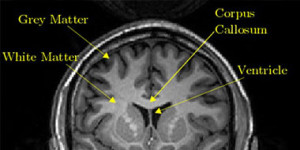

Injury to Brain MatterWhite vs. Grey Matter Injury

Brain damage is often described as either a white or grey matter injury, but what is the difference?

White matter injuries occur when white matter tracts (bundles of myelinated axons) are damaged. Damage essentially cuts off or limits communication between areas of grey matter (neuron cell bodies and dendrites, the neuropil, glial cells, and capillaries).

Grey Matter Injuries

Neuronal death is at the heart of grey matter brain damage.

The neuron cell bodies are responsible for keeping the entire neuron alive and healthy and that takes a lot of energy. Grey matter is therefore very susceptible to injury when oxygen levels are low (hypoxia) such as during an ischemic event.